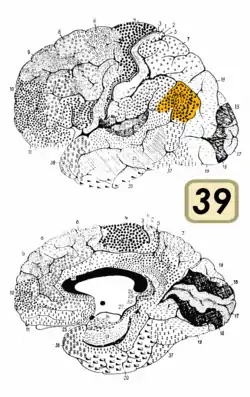

Brodmann area 39, or BA39, is part of the parietal cortex in the human brain. BA39 encompasses the angular gyrus, lying near to the junction of temporal, occipital and parietal lobes.

This area is also known as angular area 39 (H). It corresponds to the angular gyrus surrounding the caudal tip of the superior temporal sulcus. It is bounded dorsally approximately by the intraparietal sulcus. In terms of its cytoarchitecture, it is bounded rostrally by the supramarginal area 40 (H), dorsally and caudally by the peristriate area 19, and ventrally by the occipitotemporal area 37 (H) (Brodmann-1909).